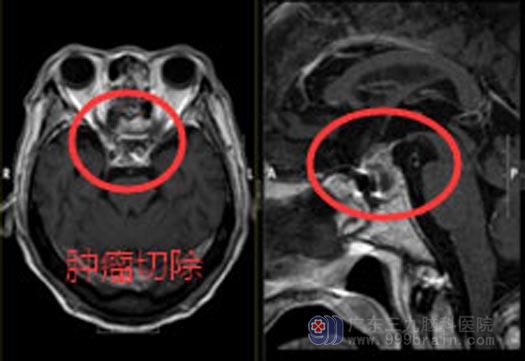

鲁明解除了他们的担忧:经鼻切除肿瘤,是不需要开颅。经鼻蝶鞍区占位切除术是鞍区占位的小创伤手术,利用直径4毫米左右的神经内镜进入鼻腔,找到鞍区脑瘤的位置,在内镜下将其切除。相比传统的开颅手术,神经内镜手术视野大,直视下操作,有利于手术医生辨认鞍区结构,减少术中对其他组织的损伤,最大程度保护鼻腔正常结构。内镜经鼻蝶手术的重要特征在于其不使用牵开器扩张鼻腔,将内镜作为照明和观察设备,利用鼻腔的生理孔道,通过逐渐收缩鼻粘膜从而扩张手术通路,避免了显微镜下因牵开器扩张所造成的鼻中隔骨折等并发症的发生;在无视觉死角的情况下,近距离直视切除肿瘤。术后患者并发症少,住院时间短、术中出血少、患者恢复快。

了解清楚后,孔大爷欣然接受了手术。术中降低对手术入路的损伤,充分暴露病灶,保护好颈内动脉和垂体,将肿瘤顺利地全部切除。术后孔大爷恢复很快,已经开心地出院了。